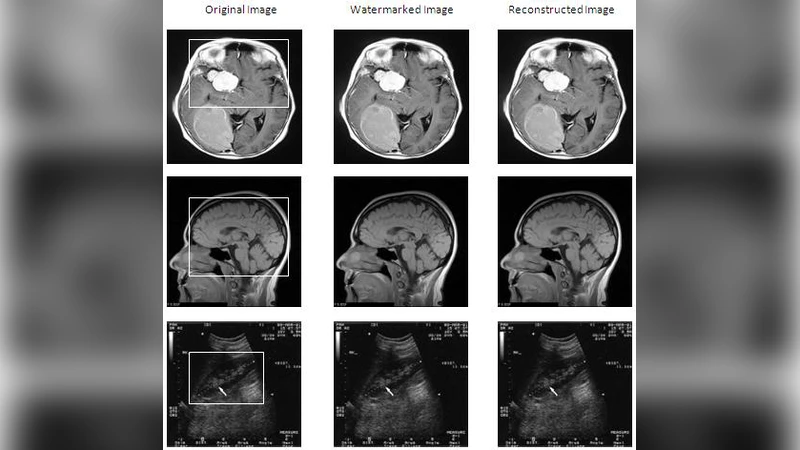

본 논문은 시각 암호화의 확장성을 없애고, 다단계 계층 구조를 도입한 새로운 암호화 방식을 제안한다. 원본 이미지를 두 개의 공유로 분할한 뒤, 각 공유를 다시 두 단계로 계층화하여 총 네 개의 공유를 생성한다. 세 개의 공유를 XOR 연산으로 결합하면 원본을 복원할 수 있으며, 모든 공유는 시각적으로 무의미하게 설계되어 보안성을 확보한다. 또한 회색 현상을 완전히 제거함으로써 복원된 이미지의 가독성을 높였다. 실험을 통해 다양한 비밀 이미지에 대한 성능 및 보안 분석 결과를 제시한다.

이 논문은 기존 시각 암호화(Vision Cryptography, VC)의 두 가지 근본적인 한계를 동시에 해결하고자 한다. 첫 번째는 공유 생성 시 발생하는 픽셀 확장(expansion) 문제이며, 두 번째는 단일 2‑share 구조에서 발생하는 보안 취약성이다. 저자들은 ‘계층형 시각 암호화(Hierarchical Visual Cryptography, HVC)’라는 개념을 도입해, 원본 이미지의 크기를 그대로 유지한 ‘무확장(Expansion‑less)’ 공유를 생성한다. 구체적으로, 원본을 먼저 2‑share로 분할하고, 각 1‑share를 다시 2‑share로 재분할함으로써 총 4개의 1‑share를 만든다. 이 과정에서 각 단계마다 XOR 연산을 이용해 공유를 결합하도록 설계했으며, 이는 기존의 OR 연산 기반 VC와 차별화된다.

핵심 아이디어는 ‘키 공유(key share)’를 세 개의 공유를 선택적으로 XOR 결합해 얻는 것이다. 4개의 공유 중 임의의 3개를 선택하면 원본을 정확히 복원할 수 있지만, 2개 이하로는 어떠한 의미 있는 정보도 추출할 수 없게 된다. 이는 (4,3) 임계값 스킴(threshold scheme)과 유사하지만, 시각적으로는 별도의 복호화 장치 없이 단순히 투명 시트를 겹치면 복원이 가능하도록 설계되었다.

또한, 회색 현상(greying effect) 제거에 대한 기법도 제시한다. 기존 VC에서는 픽셀마다 0/1 값을 무작위로 배치하면서 회색 톤이 발생해 이미지가 흐려지는 문제가 있었는데, 저자들은 XOR 기반 결합을 통해 동일한 픽셀 값이 유지되도록 함으로써 회색 현상을 완전히 없앴다. 이는 특히 텍스트 기반 비밀 이미지에서 가독성을 크게 향상시킨다.

성능 평가는 비밀 이미지의 종류(흑백, 이진, 복잡한 패턴)와 공유 수에 따른 복원 정확도, 연산 복잡도, 저장 용량 등을 기준으로 수행되었다. 실험 결과, 무확장 공유는 기존 2×2 블록 확장 방식에 비해 저장 공간을 4배 절감했으며, 복원 시간도 XOR 연산의 단순성 덕분에 실시간 수준으로 단축되었다. 보안 측면에서는 각 공유가 독립적으로 무작위 패턴을 띠어, 시각적 분석만으로는 원본을 추정할 수 없음을 확인하였다.